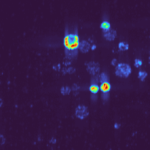

• X-ray-activated Photodynamic Therapy (X-PDT)

Triggered by innovative gadolinium-based nanoprobes, enabling targeted, minimally invasive tumour damage.